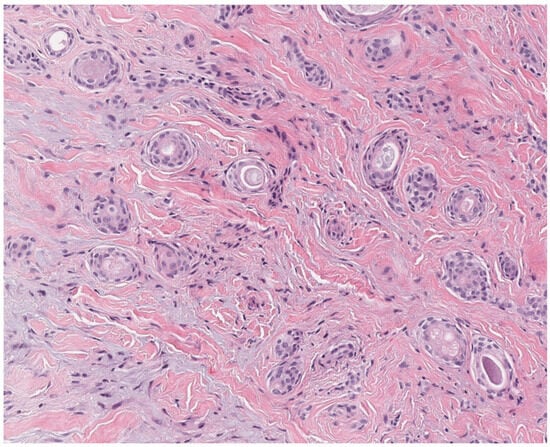

2.2. Tricholemmoma

- Gustafson, S.; Zbuk, K.M.; Scacheri, C.; Eng, C. Cowden syndrome. Semin. Oncol. 2007, 34, 428–434. [Google Scholar] [CrossRef]

- Kaptan, M.A.; Kattampallil, J.; Rosendahl, C. Trichilemmoma in continuity with pigmented basal cell carcinoma; with dermatoscopy and dermatopathology. Dermatol. Pract. Concept. 2015, 5, 57–59. [Google Scholar] [CrossRef]

- Tardío, J.C. CD34-reactive tumors of the skin. An updated review of an ever-growing list of lesions. J. Cutan. Pathol. 2009, 36, 89–102. [Google Scholar] [CrossRef]

- Romano, C.; Schepis, C. PTEN gene: A model for genetic diseases in dermatology. Sci. World J. 2012, 2012, 252457. [Google Scholar] [CrossRef]

- Al-Zaid, T.; Ditelberg, J.S.; Prieto, V.G.; Lev, D.; Luthra, R.; Davies, M.A.; Diwan, A.H.; Wang, W.; Lazar, A.J. Trichilemmomas show loss of PTEN in Cowden syndrome but only rarely in sporadic tumors. J. Cutan. Pathol. 2012, 39, 493–499. [Google Scholar] [CrossRef] [PubMed]

- Hobert, J.A.; Eng, C. PTEN hamartoma tumor syndrome: An overview. Genet. Med. 2009, 11, 687–694. [Google Scholar] [CrossRef] [PubMed]